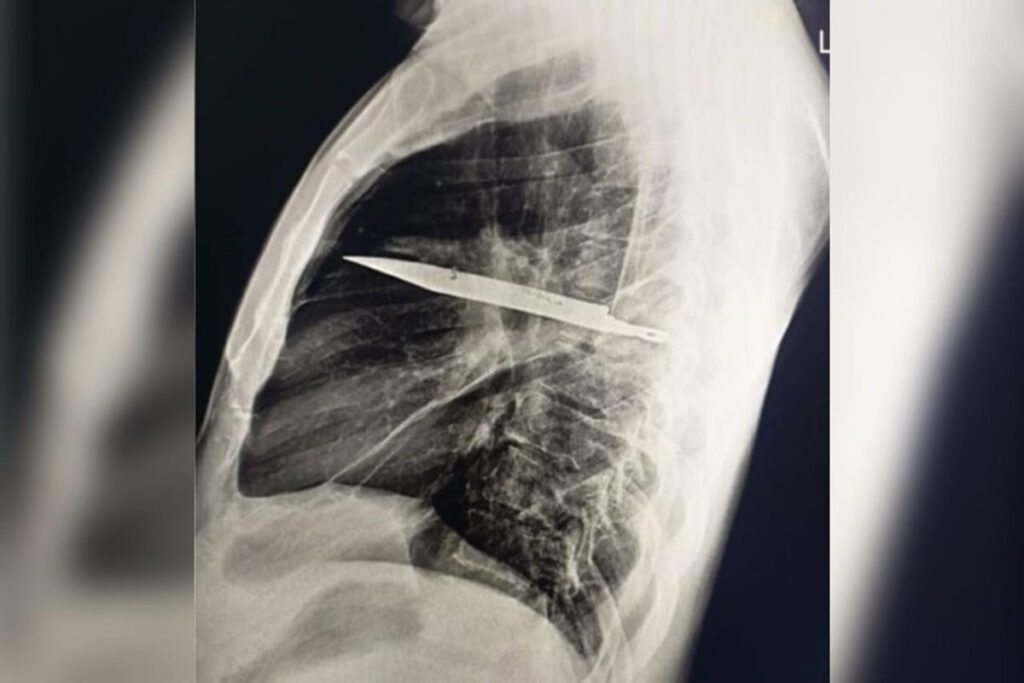

Homem sente dor no peito e descobre faca alojada no corpo há oito anos

Um homem de 44 anos descobriu que viveu por oito anos com uma faca alojada no peito sem saber. A revelação veio depois que ele procurou atendimento médico na Tanzânia por causa de secreção com mau cheiro logo abaixo do mamilo direito.

No caso, publicado no Journal of Surgical Case Reports em 31 de maio, o paciente relatou que não sentia dor no peito, dificuldade para respirar, tosse ou febre, e apresentava sinais vitais normais, o que deixou os médicos intrigados.

Enquanto os profissionais investigavam o caso, o paciente lembrou que, quase dez anos antes, havia se machucado durante uma briga, sofrendo cortes no rosto, nas costas, no tórax e no abdômen. Na época, recebeu suturas, mas não passou por exames de imagem, já que não havia suspeita de que algum objeto tivesse permanecido no corpo.